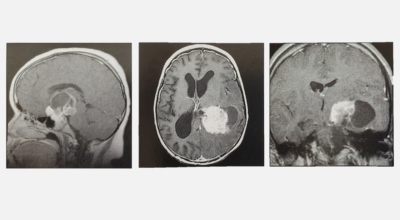

뇌종양이란 뇌 조직이나 뇌를 싸고 있는 막에서 발생한 종양과, 머리뼈나 주변 구조물로부터 멀리 떨어진 부위에서 뇌 조직이나 뇌막으로 전이된 종양을 의미해요. 뇌종양은 양성과 악성으로 나눌 수 있습니다. 양성 뇌종양은 성장 속도가 느리며 주위 조직과의 경계가 뚜렷해요. 양성 뇌종양은 수술 이외의 다른 치료 없이 완치되는 경우가 흔하고, 대부분 천천히 자라기 때문에 수술하지 않고 경과를 관찰하기도 해요. 그러나 양성 뇌종양도 완치될 수 없는 경우가 있습니다.

뇌간이나 척수와 같은 특정 부위에 발생된 종양은 수술로 없앨 수 없습니다. 또 크기가 작더라도 생명에 중요시되는 기능을 담당하는 뇌와 척수에 정도가 심한 훼손을 입힐 수 있답니다. 이 경우 조직학적으로는 양성이지만, 임상적으로는 악성과 같습니다. 악성 뇌종양은 뇌암이라고도 하고, 성장 속도가 빠르며 주위 조직으로의 침투 역량이 강해요. 이에 따라 정상 뇌 조직으로 침윤되고 정상 뇌 조직과의 경계가 불분명해서 치료가 어려운 편이예요. 악성 뇌종양은 주변의 정상 뇌 조직을 빠른 속도로 파괴해요.